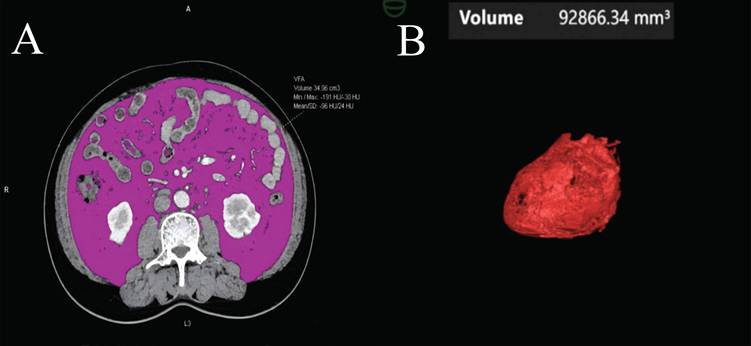

2.2.3 Visceral Fat Deposition Measurement

Abdominal CT images obtained during the portal venous phase at diagnosis were analyzed using body composition analysis software (Syngo.via Client 10.6, Germany). The software automatically detects the third lumbar vertebra (L3) and measures visceral fat area (VFA) (Figure 2A), subcutaneous fat area (SFA), skeletal muscle area (SMA), and intermuscular fat area (IMFA) at the L3 level [15-17]. Renal sinus fat (RSF) [18, 19], hepatic steatosis, and epicardial adipose tissue (EAT) volume [20-23] were also quantified (Figure 2B) (Supplementary Material).

Figure 2

Visceral fat and epicardial adipose tissue volume measurements from a CT scan. (A) The visceral fat area (VFA) was measured at the third lumbar vertebra. Within this region of interest, pixels between -190 and -30 Hounsfield Units were accounted as fat. (B) After 3-dimensional reconstruction, EAT volume was calculated by summation of all pixels accounted as fat.